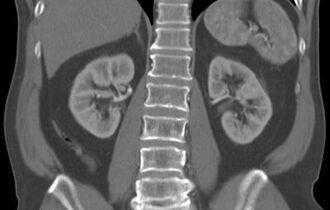

Туберкулез почки

- милиарный туберкулез характеризуется множественными очагами поражения (до 2 мм), локализованными во всех сегментах легких, часто обнаруживают патологии в печени, почках, кишечнике, селезенке, мозге, костях. Данный вид заболевания имеет неблагоприятный прогноз и высокую скорость прогрессии. Поэтому важна ранняя диагностика.